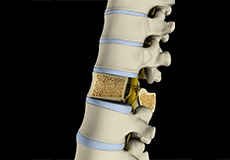

Herniated Disc (Lumbar)

Herniated disc is a condition in which the outer fibers (annulus) of the intervertebral disc are damaged causing the soft inner material of the nucleus pulposus to rupture out of its space. A herniated disc, common in the lower back (lumbar spine) occurs when there is a tear in the outer lining of the disc (annulus fibrosus). This causes the inner jelly-like material (nucleus pulposus) to leak out and place pressure on the adjacent spinal nerve root. It is the most common cause of lower back pain and pain that radiates down the leg (radiculopathy).

Lumbar Herniated Disc

A herniated disc is a condition in which the outer fibers (annulus) of the intervertebral disc are damaged, causing the soft inner material of the nucleus pulposus to rupture out of its space. It is the most common cause of lower back pain and pain that radiates down the leg (radiculopathy).

Lumbar Disc Herniation

Lumbar disc herniation is the most common cause of lower back pain and leg pain (sciatica). Aging, injury or trauma may cause the annulus fibrosus to tear, resulting in protrusion of the nucleus pulposus. This may compress the spinal nerves and/or spinal canal.

Disc Herniation

Disc herniation is a condition where the central nucleus pushes through the outer edge of the disc, causing a bulge that compresses the spinal nerves.